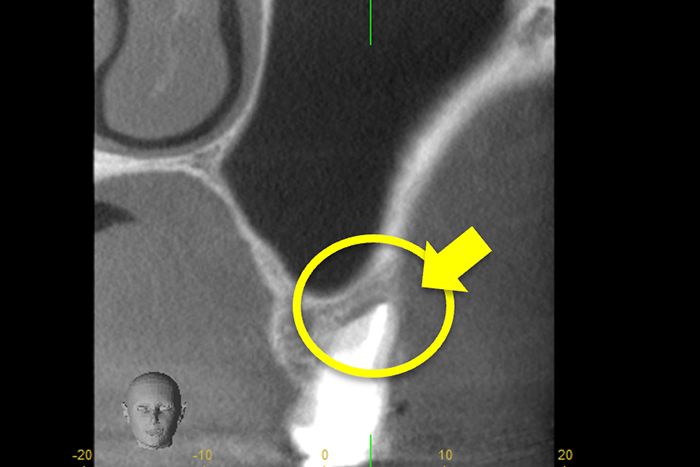

更に、拡大すると歯根破折に加え、器具の破折片も確認できる。

心臓の鼓動のように『ドク・ドク』と浸出液が出ているのが分かる。